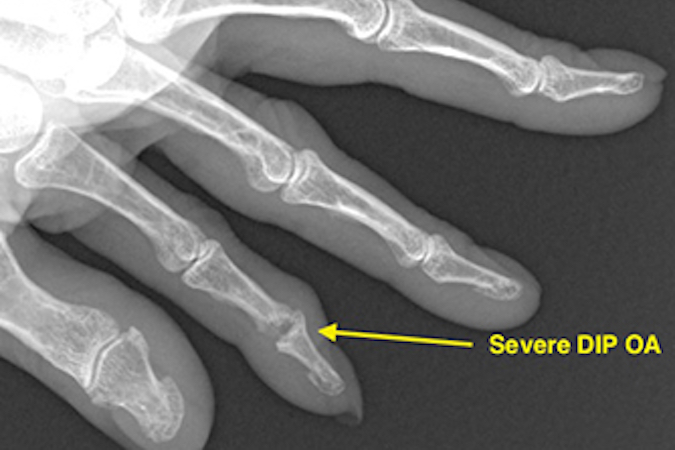

• Severe index DIP OA with bone loss (arrow).

Severe index DIP OA with bone loss (arrow).